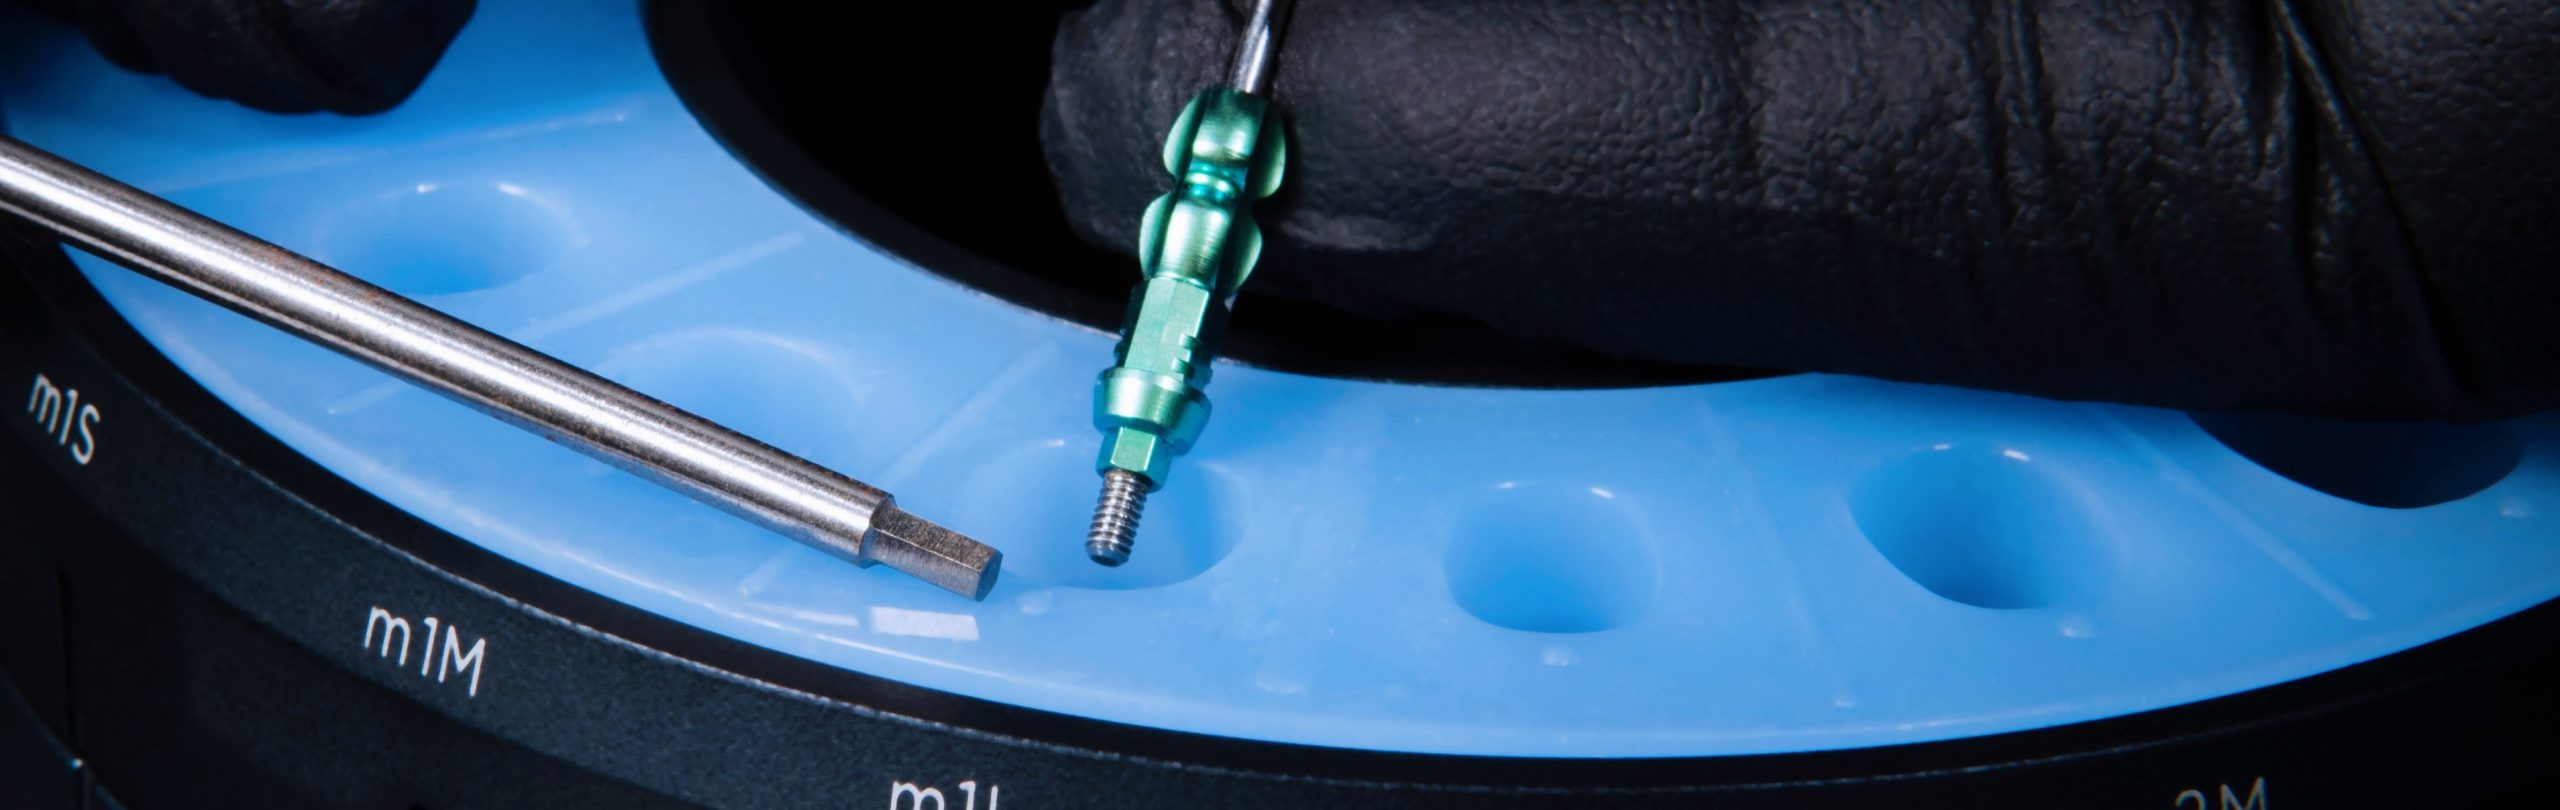

Pasul 3 – Procesul de fabricare a pilonului de vindecare personalizat

Rotește inelul superior al matriței până când forma/ dimensiunea dorită a puțului de silicon este aliniată la inserția protetică VPI dorită, prezentă în baza matriței.

Poziția fiecărei inserții de conexiune protetică VPI în interiorul bazei matriței ar trebui să fie disponibilă pe fișa informativă care însoțește kitul matriței. Acest lucru va facilita procesul de identificare a poziției inserțiilor de conectare de tip implant pentru asistent.

Pasul 4 – Procesul de fabricare a pilonului de vindecare personalizat

Asistentul instalează un bont temporar în puțul matriței cu codul corespunzător (E.g pS) la cel din fila de formă anatomică a ghidului (E.g pS).

El / Ea introduce apoi materialul compozit adecvat în spațiul deschis și vindecă ușor cu unul sau mai multe trepte.

Apoi dezinstalează bontul personalizat de vindecare creat și continuă cu lustruirea suprafeței compozite și dezinfectarea corespunzătoare.

Procesul de fabricare a bontului de vindecare personalizat se poate face după programarea consultației sau chiar la o intervenție chirurgicală, deoarece necesită doar aproximativ 4 minute pentru a fi finalizată.